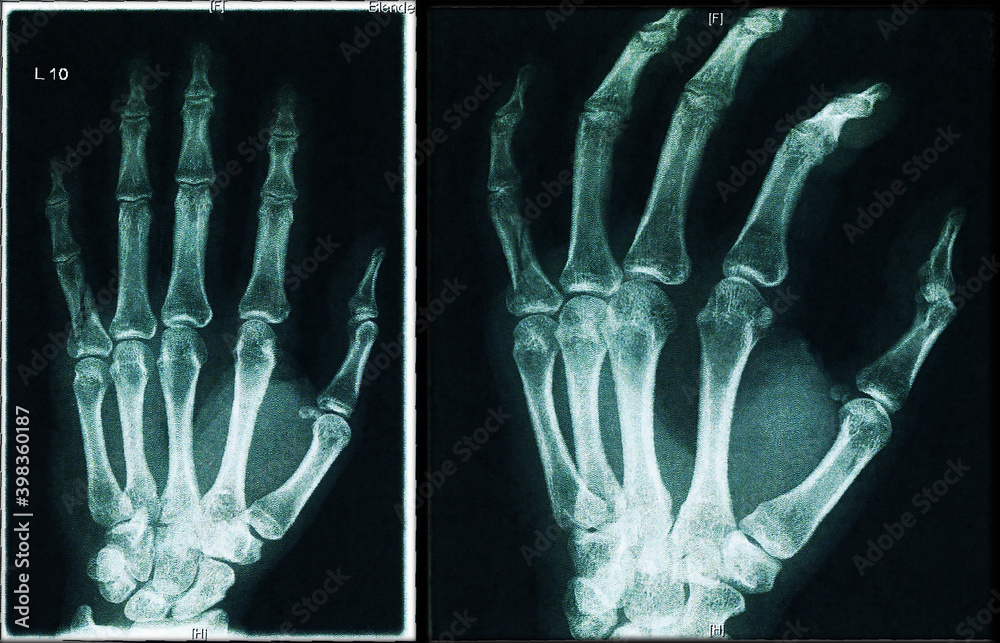

Fingergrundgliedfraktur Handchirurgie Dr. Paul Preisser